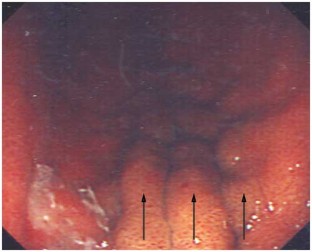

Background A 35-year-old woman with a past history of antiphospholipid syndrome and near-fatal vascular thrombosis was transferred to Glasgow Royal Infirmary, UK, for investigation of 'obscure' gastrointestinal bleeding in the context of long-term oral anticoagulation therapy. Initial endoscopic examination revealed isolated gastric varices with stigmata of recent hemorrhage. She had no prior history of liver disease or portal hypertension. Investigations to ascertain the cause of her varices were performed.

Diagnosis Nodular regenerative hyperplasia of the liver leading to gastric varices.